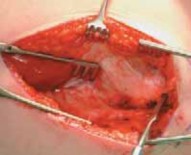

Wound Closure

3. The vastus lateralis is reattached to its origin on the trochanteric ridge with absorbable braided 0 suture so that the entire plate is covered (

TECH FIG 5

). Two or

three tacking sutures are used to reattach the posterior edge of the vastus fascia to the septum.

--- TECH FIG 5 • Repair of vastus lateralis to its origin to cover the blade plate. #### PROXIMAL FEMORAL DEROTATIONAL OSTEOTOMY WITH 90-DEGREE AO BLADE PLATE: PRONE TECHNIQUE18